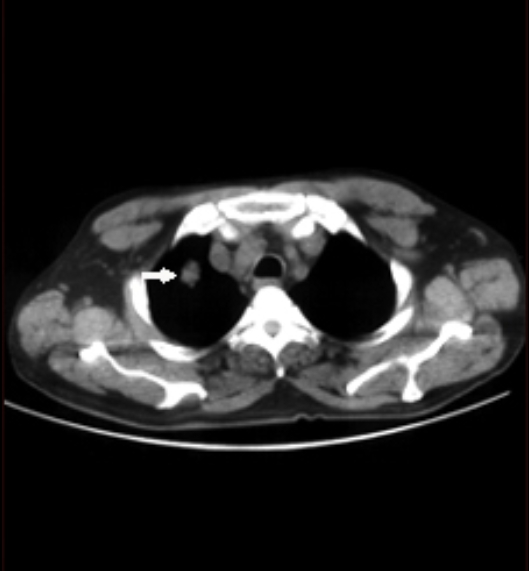

폐 편평세포암은 폐암의 한 유형으로, 주로 흡연과 관련이 있습니다. 기침이 3주 이상 지속되거나 피 섞인 가래, 숨이 차는 증상이 있으면 검사를 받아야 합니다. 흡연자는 비흡연자보다 편평세포암 발생 위험이 몇 배나 높습니다. 금연은 가장 강력한 예방책이며, 폐 건강을 지키는 가장 직접적인 방법입니다.

진단은 흉부 X선, CT, 기관지 내시경, 조직검사로 이뤄집니다. 치료는 수술, 방사선, 항암치료, 면역치료가 병합됩니다. 최근에는 맞춤형 치료제가 도입되어 생존율이 향상되고 있습니다.